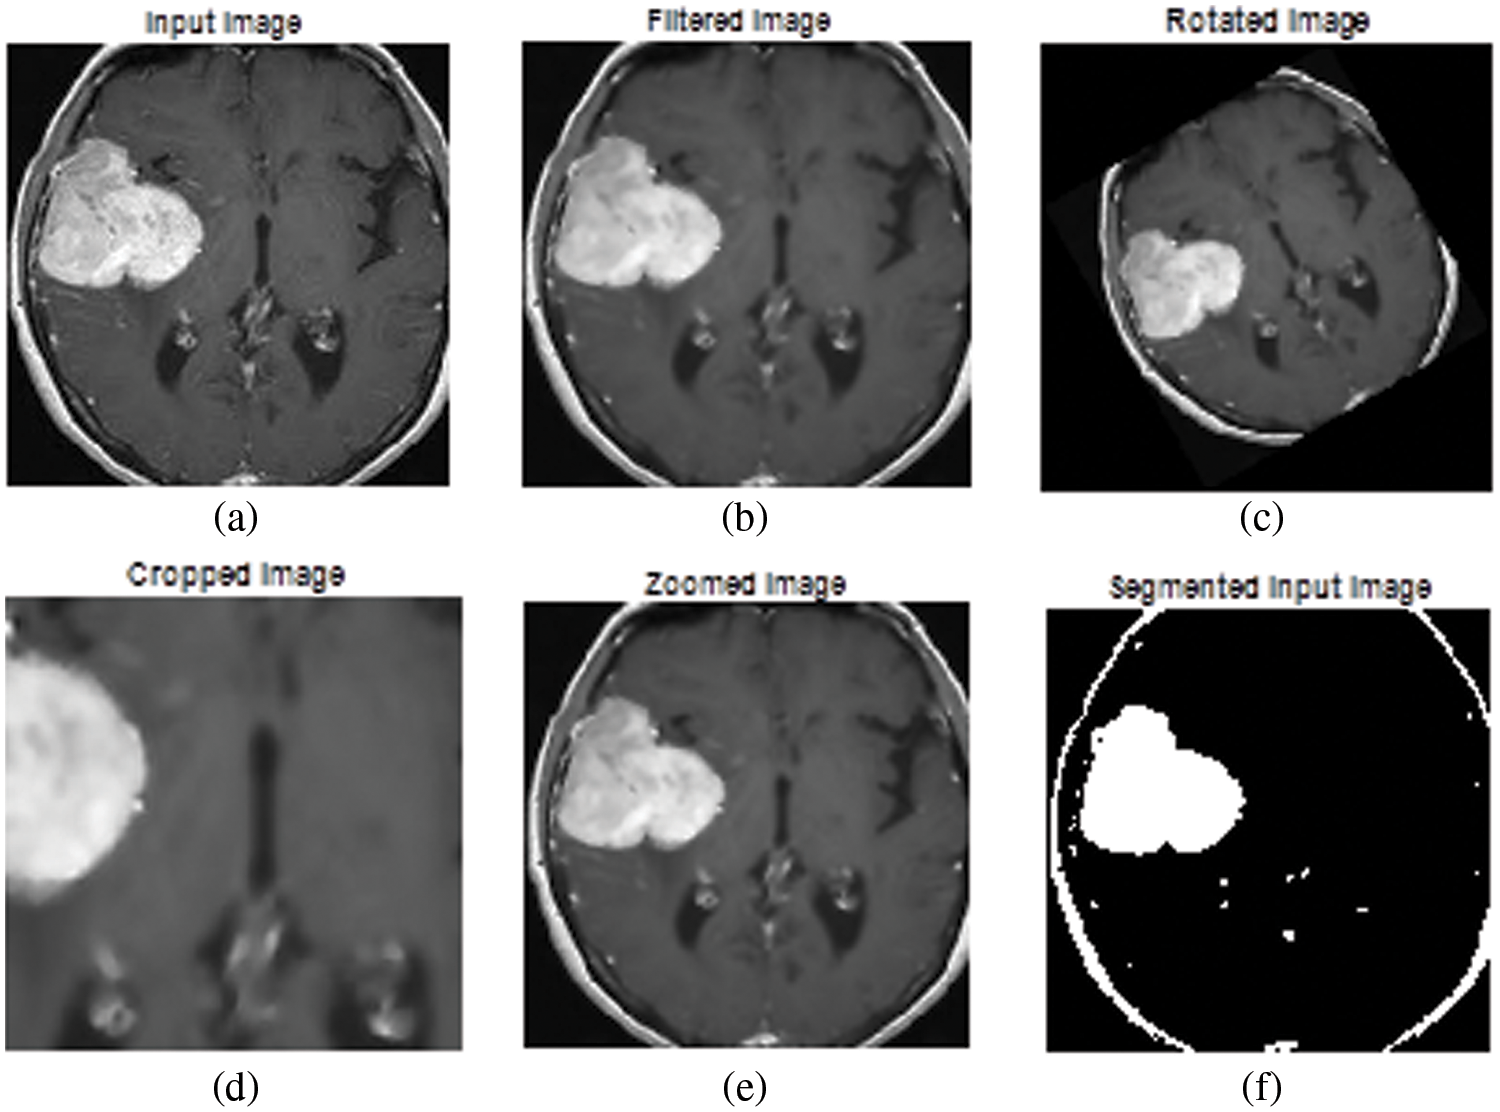

The experimental results of the proposed tumor classification are presented in this section. The proposed approach is implemented using MATLAB with windows 10 and 4 GB RAM. The performance of the proposed approach is analyzed based on different metrics. For experimental analysis images were collected from the UCI Machinery laboratory. The image’ test results are shown in Fig. 4. Fig. 4a depicts the original image, whereas Fig. 4b depicts the filtered version of the primitive image. The rotated image is exposed in Fig. 4c, while the cropped image is shown in Fig. 4d. Figs. 4e and 4f depict a zoomed-in picture and a segmented image. The Wiener filter is used to expel any distortion and noise from the primary picture. With the optimal pixel count, this image seems perfectly obvious. MATLAB is used throughout the whole brain tumor categorization procedure. A confusion matrix is presented in Fig. 5.

Figure 4: Experimental results (a) primary image, (b) filtered image, (c) rotated image, (d) cropped image, (e) zoomed image, and (f) segmented output